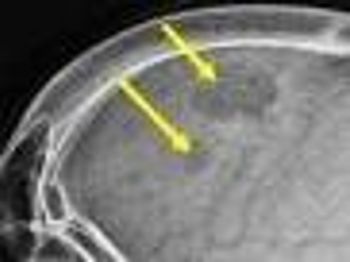

A 92-year-old woman presented with a 6-month history of progressively worsening fatigue, weight loss, generalized bone pain, and dyspnea on exertion. A skeletal survey found lytic lesions in the pelvis, sacrum, and calvarium (shown here).